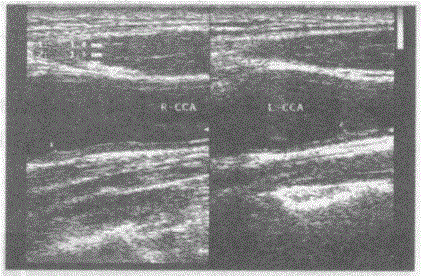

问题 临床资料:男,52岁,常规体检,确诊糖尿病、高血压、高血脂3年余。 超声综合描述:双侧颈总动脉内膜粗糙,连续中断,中内膜回声强弱不均,节段性增厚,分叉处最大厚度:左0.14cm。右0.13cm。 超声提示:

选项 A.双侧颈动脉粥样硬化并软斑形成 B.双侧颈动脉粥样硬化并钙化斑形成 C.双侧颈动脉轻度粥样硬化(节段性中内膜增厚) D.正常颈动脉声像图

答案 C